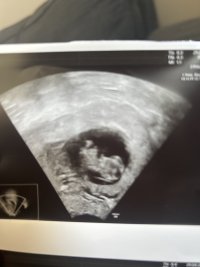

Såå søtBle målt til 8+2 så 1 dag fremMen til venstre kan dere se en muskelknute i livmora… noen som har erfaringer med det? Da jeg leste om det ble jeg litt bekymret og det ga plutselig mening hvorfor jeg har hatt vondt rundt menstrasjon og mistet noen ganger…

da var jeg 8+1.